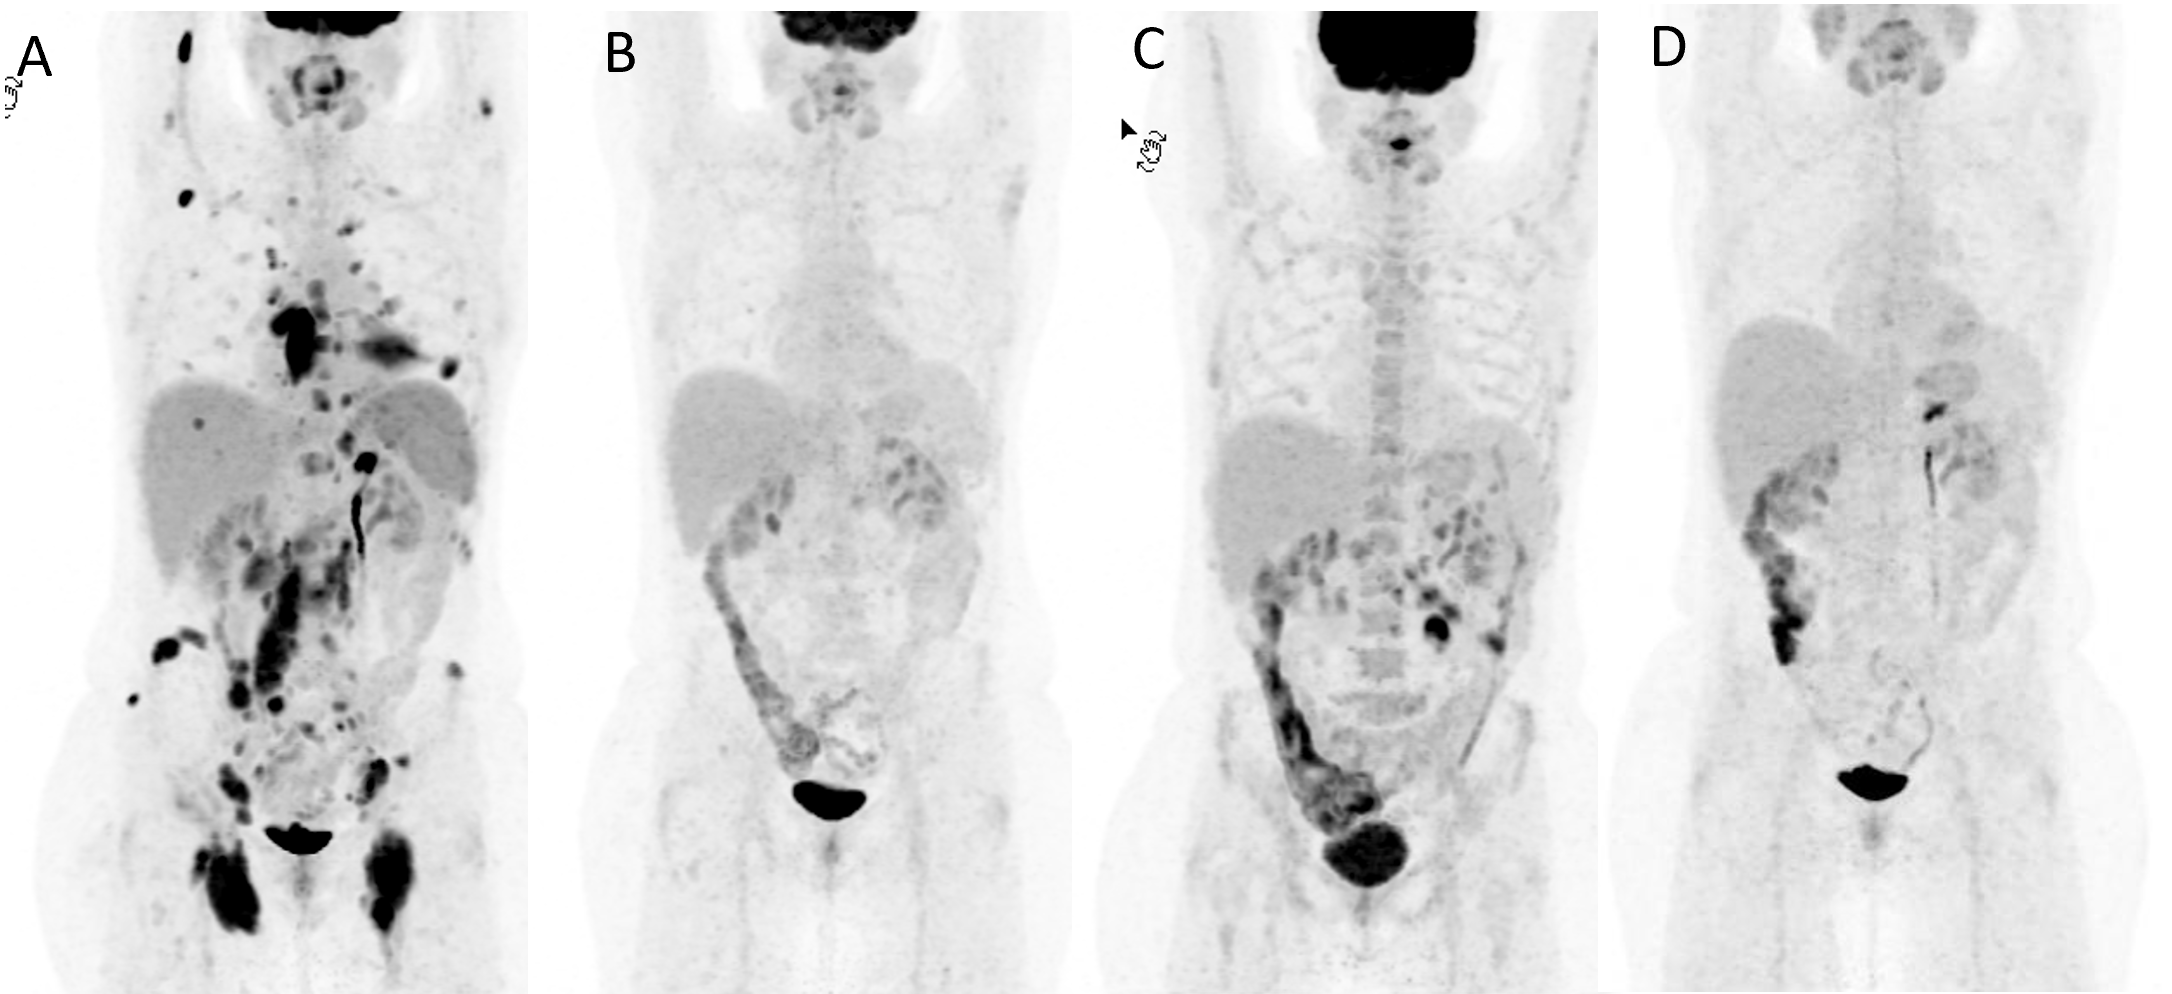

Biopsy shows infiltration of mesenteric fat with large numbers of lipid-laden macrophages that may be biologically avid for 18F-FDG.2,7 (Figures 1&2)

Figure 2 PET/CT, CT and PET images of mesenteric panniculitis (MP) mimicking a lymphoma recurrence (A) and its resolution after about three weeks without changes in the treatment (B).